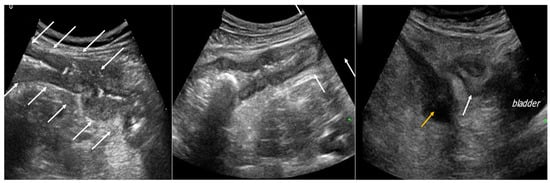

4. Acute Appendicitis

5. Acute Diverticulitis

6. Bowel Obstruction

6.1. GIUS Signs of SBO

6.2. GIUS Signs of LBO

7. Gastrointestinal Perforation